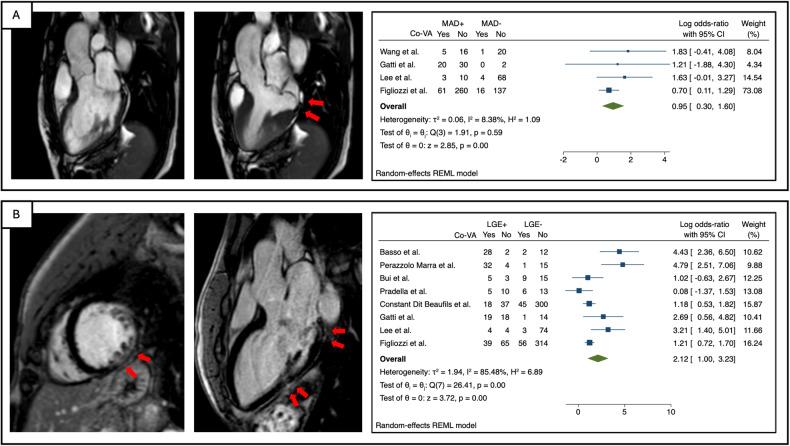

The meta-analysis included 11 studies with 1278 patients. MR severity, leaflet length/thickness, curling, MAD distance, and mapping techniques were not meta-analyzed as reported in < 3 studies. LV end-diastolic volume index, LV ejection fraction, and prolapse distance showed small non-significant effect sizes. LGE showed a strong and significant association with co-VA with a LogORs of 2.12 (95% confidence interval (CI): [1.00, 3.23]), for MAD the log odds-ratio was 0.95 (95% CI: [0.30, 1.60]). The predictive accuracy of LGE was substantial, with a hierarchical summary ROC AUC of 0.83 (95% CI: [0.69, 0.91]) and sensitivity and specificity rates of 0.70 (95% CI: [0.41, 0.89]) and 0.80 (95% CI: [0.67, 0.89]), respectively.

Our study highlights the role of LGE as the key CMR feature for arrhythmia risk stratification in MVP patients. MAD might complement arrhythmic risk stratification.

LGE is a key factor for arrhythmogenic risk in MVP patients, with additional contribution from MAD. Combining MRI findings with clinical characteristics is critical for evaluating and accurately stratifying arrhythmogenic risk in MVP patients.